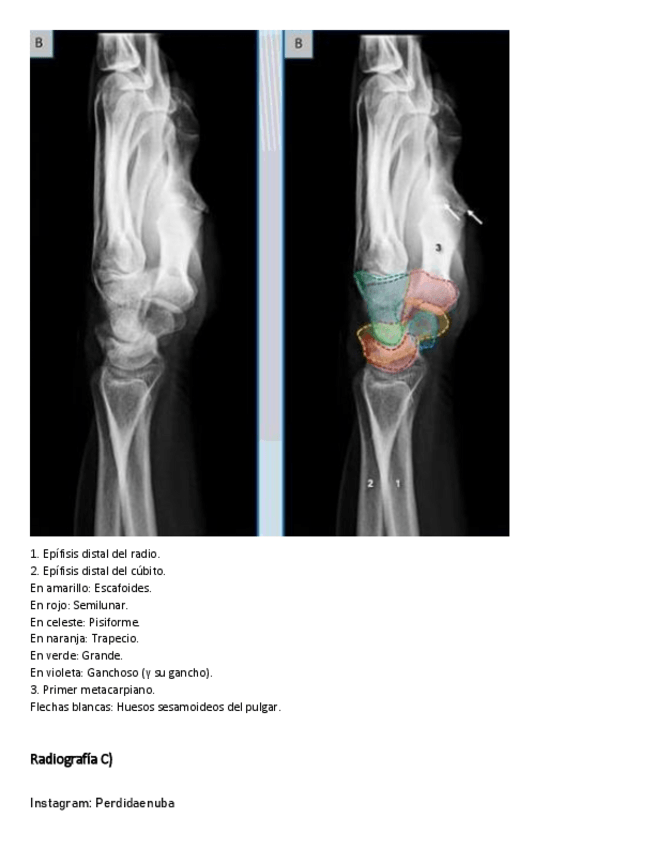

He publicado nuevos apuntes de 8º Cirugía General: MANO-Y-MUNECA.pdf